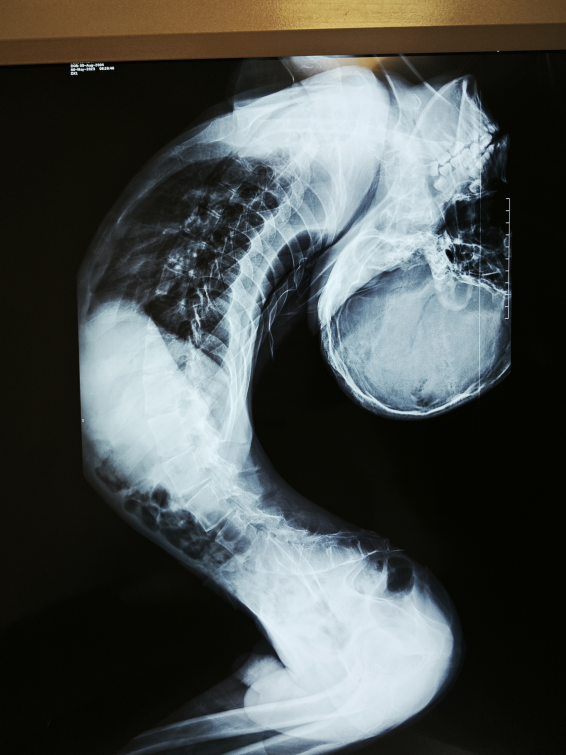

姜延琛的术前影像资料

这场手术的难度远超常规脊柱矫形,根源在于脊柱反向折叠的特殊性。与常见 “驼背”(正向折叠)不同,反向折叠患者的脊柱向反方向弯曲、拉长,胸腔薄如纸,肋骨无法膨胀,膈肌因胸腹腔高压难以下降。“从肚子上摸甚至能摸到主动脉,胸腔腹腔的整个前后径都很短,呼吸空间极度狭小,引起了呼吸衰竭。”梁益建说。

且姜延琛的肺功能仅为正常人的20%,还伴有重度骨质疏松,骨质甚至达不到60岁女性的水平,这些都为手术增加了难度。手术中还需考虑麻醉、呼吸障碍、大出血、瘫痪、循环衰竭等危急情况的紧急预案。

“就像在深井里操作,周围全是重要结构。”梁益建这样描述手术环境的严苛:脏器挤在狭长体腔内,腹腔高压使静脉血主要通过椎管内静脉丛回流,手术全程出血量较大,视野不清;脊髓被拉长变细,周围缠绕大量静脉丛,一旦损伤便意味着瘫痪;姜延琛既往手术导致颈椎解剖结构破坏,颈椎前后截断操作需精准避开椎动脉,毫米级偏差都可能致命。团队创新采用“反向截骨”方案,将拉长的脊柱矫正成类似“驼背”的状态以创造空间。